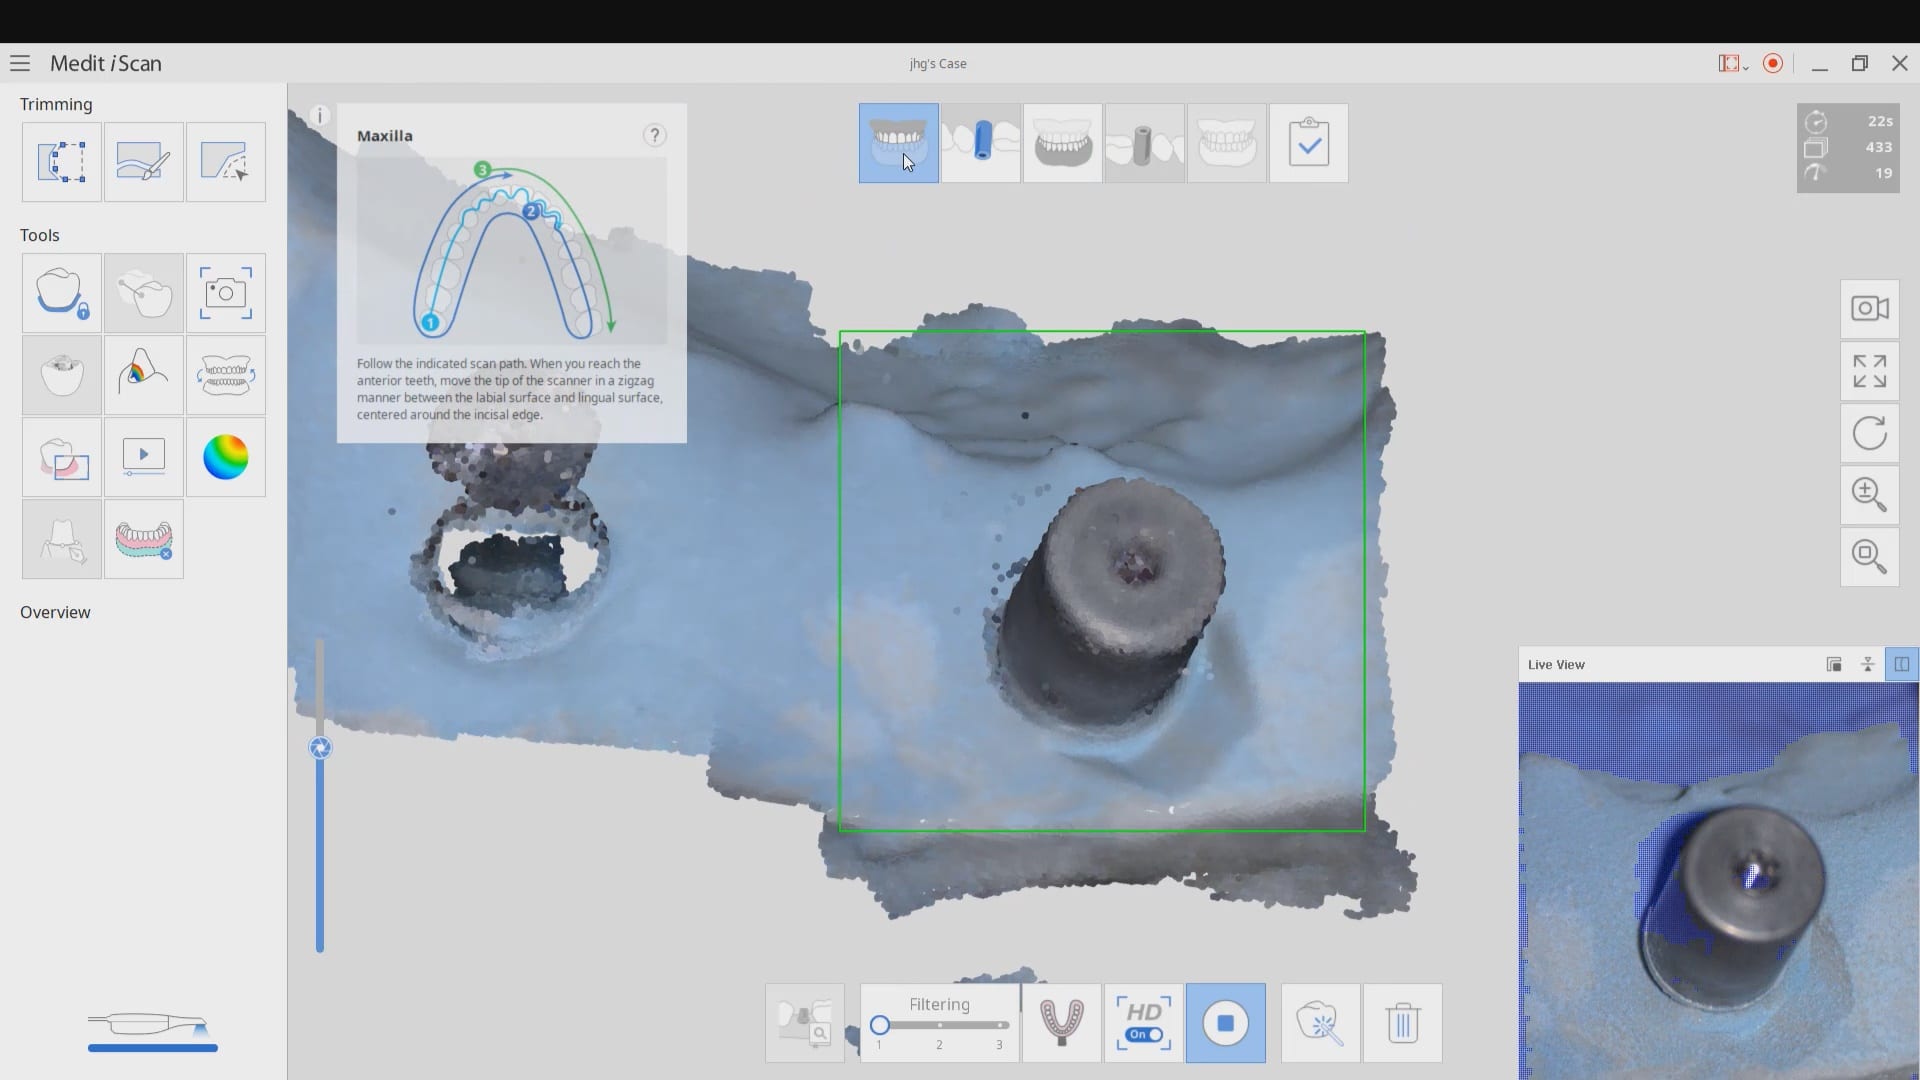

Mixing Photogrammetry and Intra-Orals Scanner by Medit i500

February 4, 2020To date, the literature and research clearly points out that full arch scans with edentulous arches are prone to inaccuracies. That’s because we have never had a way to measure […]